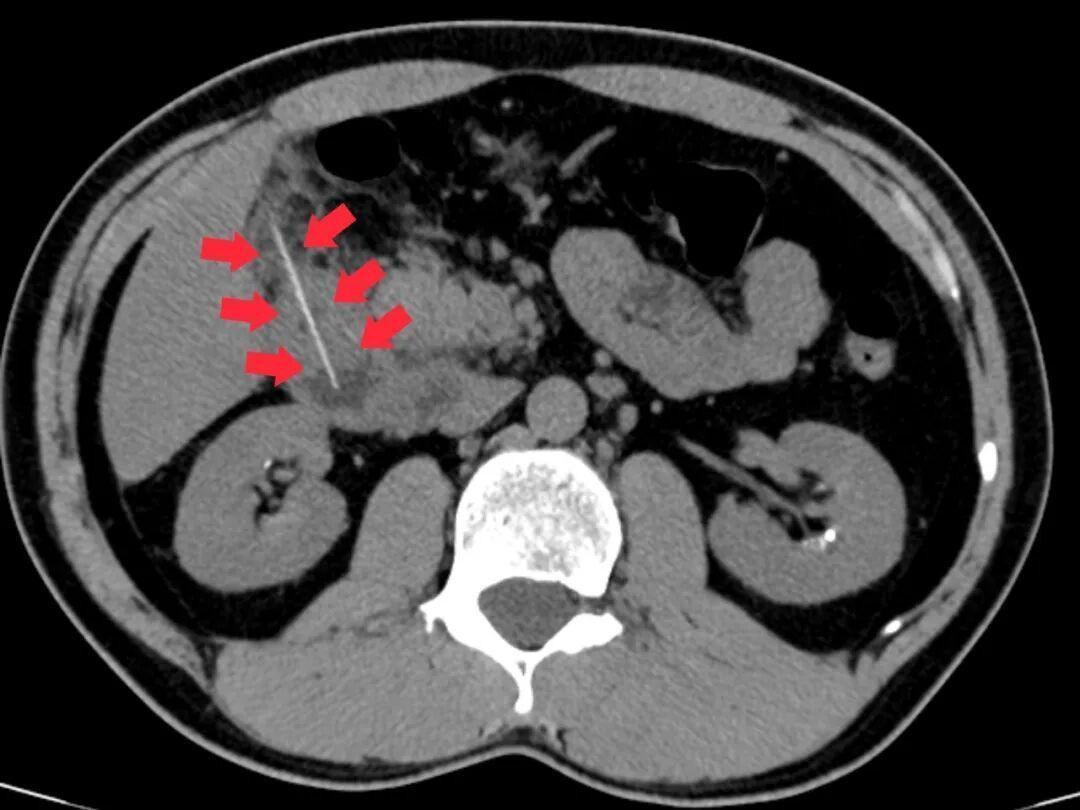

急诊科医生立即为他安排腹部CT检查,结果发现:一根牙签滞留于十二指肠降部,而且,牙签尖端已刺穿肠管壁,引发了局限性腹膜炎。

图示箭头处为异物牙签

该院外科团队火速完成术前检查,科主任麦伟锦组织多学科会诊,分析CT影像后发现,穿孔处已形成局部粘连,取出时需控制牵拉力度,决定采取“消化内镜优先、手术兜底”的双保险方案。医师李伟杰在病床前,用手机放大CT影像,通俗易懂地直观讲解治疗思路,消除了患者的疑虑。